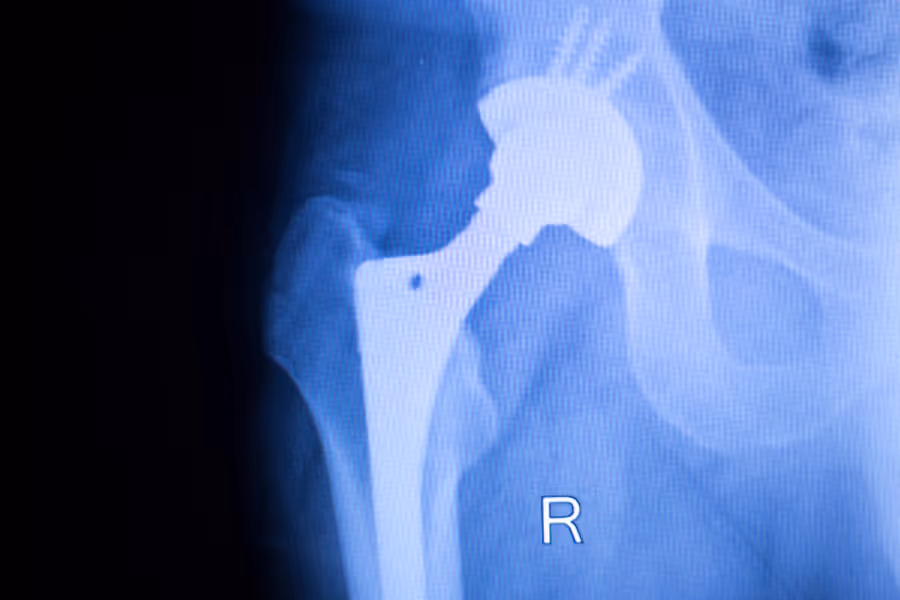

Hip replacements are a major surgery, with considerable costs. For patients paying privately, most hip replacement quotes you’ll see are in the range of:

$22,000 - $38,000+

- Hip implant / prosthesis

This is a major surgery, compared to minimally invasive hip surgery (which costs $15,000-$25,000). Private hip replacement costs vary because not every surgery is identical, and not every clinic bundles services the same way. Common price drivers include:

- Implant type and brand (your surgeon chooses what fits your anatomy and needs)

- Robotic assistance (if offered) and any additional planning requirements

What’s the difference between robotic and traditional hip replacement?

Robotic assistance can help a surgeon plan and place components with added precision tools, but recovery and outcomes still depend on many factors (surgeon technique, rehab, patient health). It’s not automatically “better” for everyone—ask what benefits are expected in your case. For more information on different techniques, read Which Method of Hip Replacement is Best?